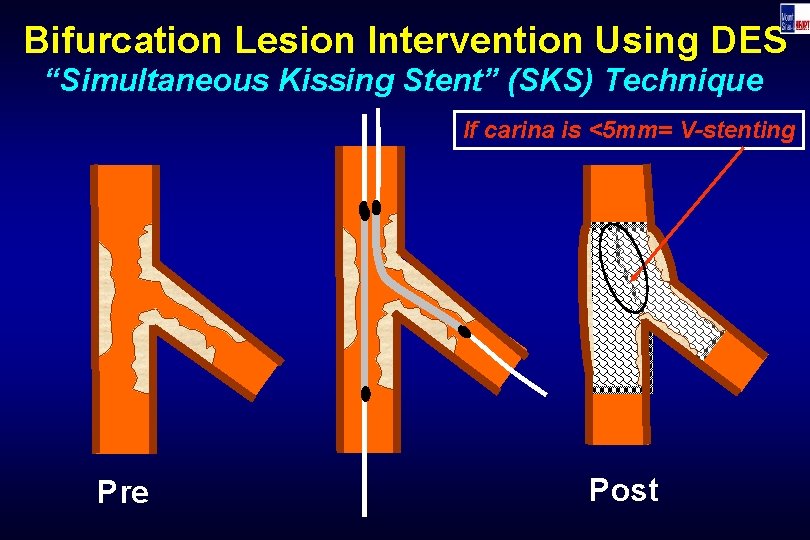

Bifurcation Lesion Intervention Using DES “Simultaneous Kissing Stent” (SKS) Technique If carina is <5 mm= V-stenting Pre Post